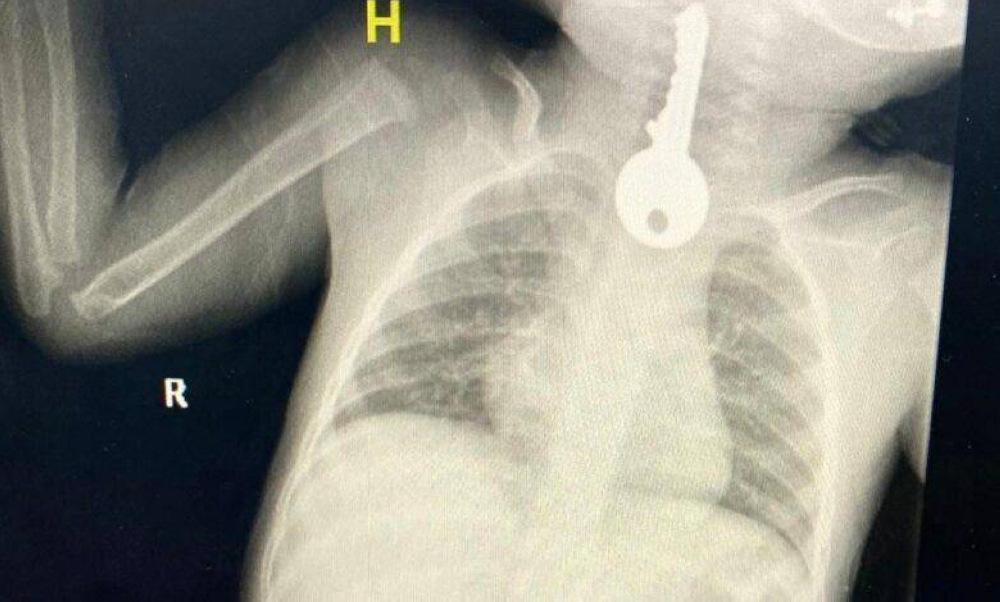

وبين مجمع الملك فيصل الطبي أنهم استقبلوا حالة طفل في وضع صحي حرج يعاني من ضيق في التنفس مما استدعى تقديم الإسعافات الأولية وإجراء الفحوصات السريرية والإشعاعية التي كشفت وجود جسم غريب على شكل مفتاح في المريء.

وأوضح الفريق المعالج للحالة أنه تم على الفور عمل منظار عاجل واستخراج مفتاح حديدي من المريء كاد أن يودي بحياته ثم متابعته في قسم التنويم من قبل الفرق التمريضية حتى استقرت الحالة وخرج بالسلامة ولله الحمد.